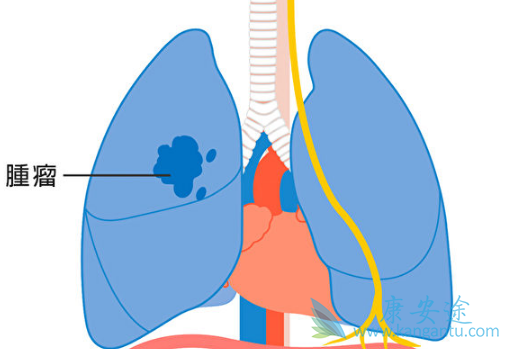

曾经奥希替尼(Osimertinib)是被批准用于一二代靶向耐药后进展的有T790M突变的肺癌患者,换言之,易瑞沙、特罗凯、凯美纳耐药后,服用奥希替尼的有效率达到60%,若患者做过基因检测,有T790M基因突变的前提下,服用奥希替尼的有效率可达64%。现在奥希替尼还可用于肺癌一线治疗,可将患者的无进展生存期延长19个月,而且对于肺癌脑转移患者,也具有明显疗效。